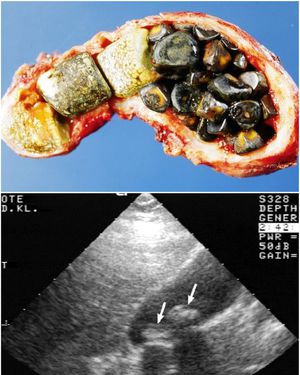

These are images of different patients suffering from cholelithiasis (defined as the presence of calculi (gallstones) within the gallbladder). The gross picture shows several different types of gallstones found within the gallbladder, the yellow gallstones consists of cholesterol whereas the outer greenish-brown stones are composed of biliverdin and stercoilin. The ultrasound picture shows stones (Hyperechoic) indicated with white arrows.Gallstones are of two types, cholesterol stones and pigmented stones. Cholesterol stones are more common up to 80%, risk factors for them are the 5Fs: Fat, Female, Forty, Flatulent, Fertile, oral contraceptives, crohn's disease, and north American Indian ancestry. Pigmented stones are either black or brown in color, they are calcium based, risk factors for them are cirrhosis, biliary stasis (strictures, dilation, biliary infection), and chronic hemolysis. Gallstones are usually asymptomatic(80%) but if the symptoms are present they are composed of biliary colic, steady, severe dull pain in epigastrium or RUQ for minutes to hours, crescendo-decrescendo pattern, frequently after fatty meal or at night, nausea, and/or vomiting. Evaluation is by ultrasound which is the test of choice of gallstones disease, radiographs can differentiate between cholesterol stones which are radiolucent (Black) from the pigmented stones which are radiopaque (White).Treatment of gallstones is cholecystectomy (Removal of the gallbladder). Complications of cholelithiasis are cholecystitis, acute pancreatitis, gallbladder cancer, choledocolithiasis, and fistula.